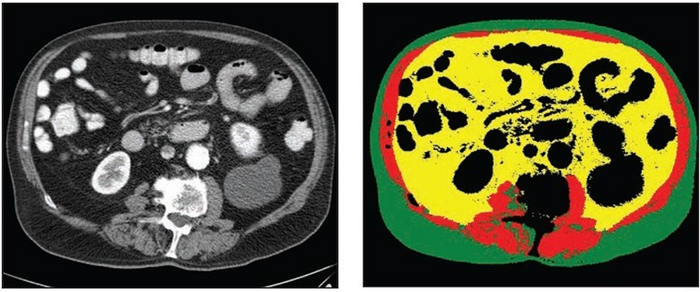

70-year-old White male patient with weight of 79.8 kg, BMI of 29.3, low cardiovascular risk factors (nonsmoker, no diabetes diagnosis, blood pressure of 120/78)

image: Left: Axial CT image at level of L3 vertebral body. Right: Matching automated segmentation label map. Visceral fat area z score is 1.41, corresponding to the 92nd percentile. Patient experienced both subsequent myocardial infarction and stroke. view more

Dr. Magudia and colleagues’ retrospective study numbered 9,752 outpatients (5,519 women, 4,233 men; 890 self-reported Black, 8,862 self-reported White; mean age, 53.2 years) who underwent routine abdominal CT at Brigham and Women’s Hospital or Massachusetts General Hospital from January–December 2012, sans a major cardiovascular or oncologic diagnosis within 3 months of examination. Fully automated deep learning body composition analysis was performed at the L3 vertebral level to determinate three body composition areas: skeletal muscle area, visceral fat area, and subcutaneous fat area. Subsequent myocardial infarction or stroke was established via electronic health records.